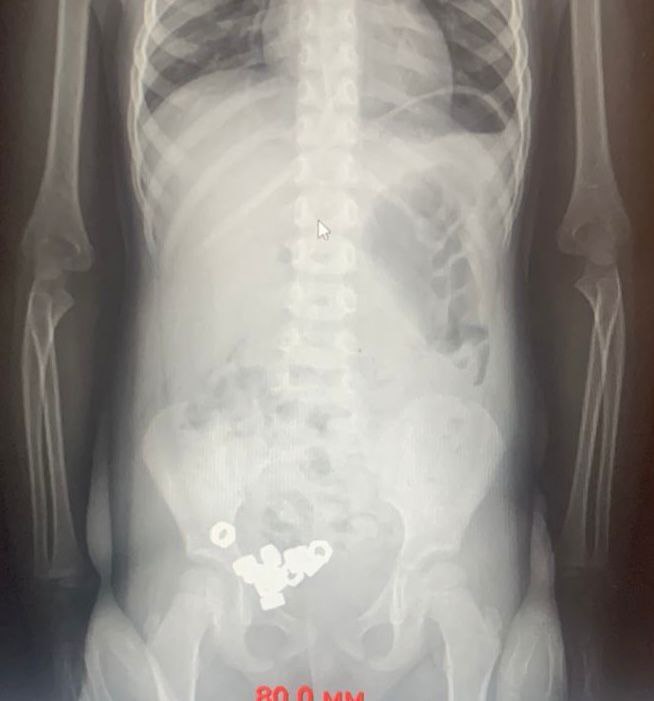

Родители трехлетнего мальчика обратились к врачам. Они предполагали, что ребенок проглотил инородные предметы. На момент осмотра симптомов не было. Однако на рентгене заметили в животе 16 маленьких гаек.